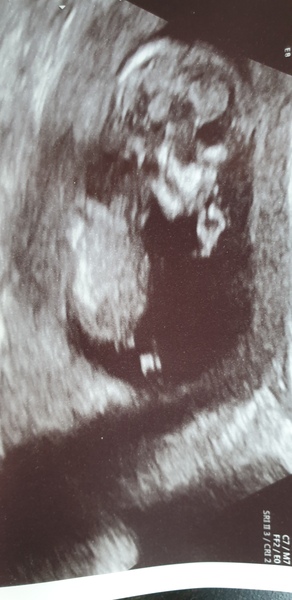

Anyway our little bean is measuring perfectly, date has moved forward a couple of days so I'm 13 weeks today which puts my due date at 9.11.20 which is not ideal as that's the anniversary of the date we found out we'd lost Isla. However we know that I won't go to full term this time, I'll either be induced or have an elective c section early. At least for today I can say I am pregnant and everything is looking good. Here's a little pic of baby sucking its thumb for you lovelies.

Pregnant after loss and dreaming of rainbows - 3

@Shefliesonherownwings yay congratulations!!! So happy for you! What an adorable scan picture 🥰

@Shefliesonherownwings so glad the scan went well, cute little thumb sucker!